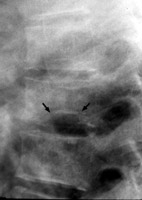

Diagnosis:Sickle cell, Gaucher's Disease Discussion:Lateral radiograph of the spine reveals central endplate depression with sparing of the anterior and posterior margins of the endplate. Several current names have been ascribed to these same changes seen in patients with hemoglobinopathy, such as Lincoln Log Sign, or H-shaped vertebra. Although not pathognomonic, these terms are typically reserved for a patient with Sickle-Cell disease. References: